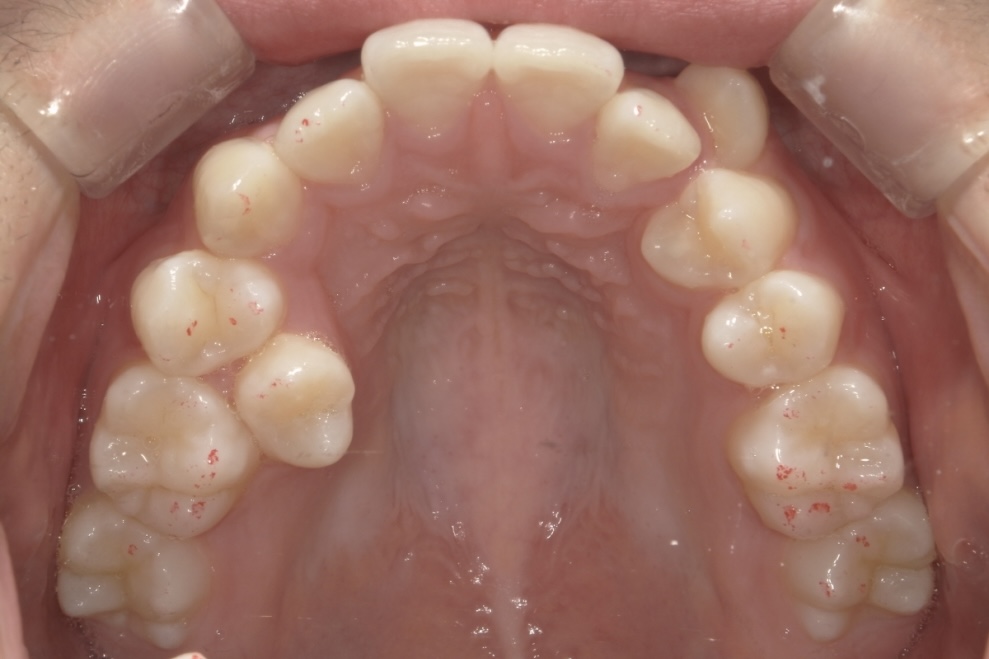

高校生女性 八重歯と噛み合わせが気になる

高校生の女性の患者さまで、初診時は15歳でした。八重歯と噛み合わせの乱れを主訴にご相談に来院されました。歯並びについて意識するようになったきっかけは、学校の歯科健診で矯正治療をすすめられたことだったそうです。

当院では、年齢や成長段階を正確に評価したうえで治療計画を立案し、カリエール装置を併用したマウスピース矯正を行いました。当院ではマウスピース矯正を専門的に数多く手がけてきた経験をもとに、見た目だけでなく噛み合わせの改善まで含めた治療を進めています。

八重歯や噛み合わせが整い、口元の印象が大きく改善しています。治療後には、矯正中のモチベーション維持や経過確認がしやすかった点、想定よりも早く治療を終えられたことについて、嬉しい口コミもお寄せいただきました。

BEFORE

AFTER